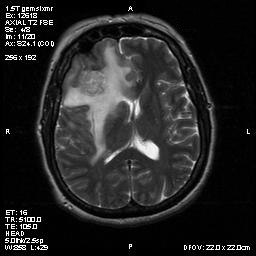

Clinical information The patient was a 54 year-old woman with a history of diabetes. She developed vomiting and frontal headache for two days. As per the descriptions of her family members, she had a few episodes of starring into the left and was unresponsive. The patient described that she could remember all these episodes clearly. On physical examination, the patient was well oriented and alert. There was no weakness in the extremities, ophthalmoplegia, diplopia, reduced visual acuity or facial weakness. An MRI and a CT scan were performed and yielded the following representative images. A surgery was performed. Representative photographs of the specimen are illustrated below.

T1-weighed MR images demonstrate an extraaxial, dural based mass involving the right supraorbital region  (Panel A and B). The mass shows homogeneous enhancement  (Panel C). CT scan demonstrates as well as rim calcification (Panel E). On T2-weighed imagers, significant vasogenic edema is demonstrated despite the small size of the lesion and the extraaxial location (Panel D).